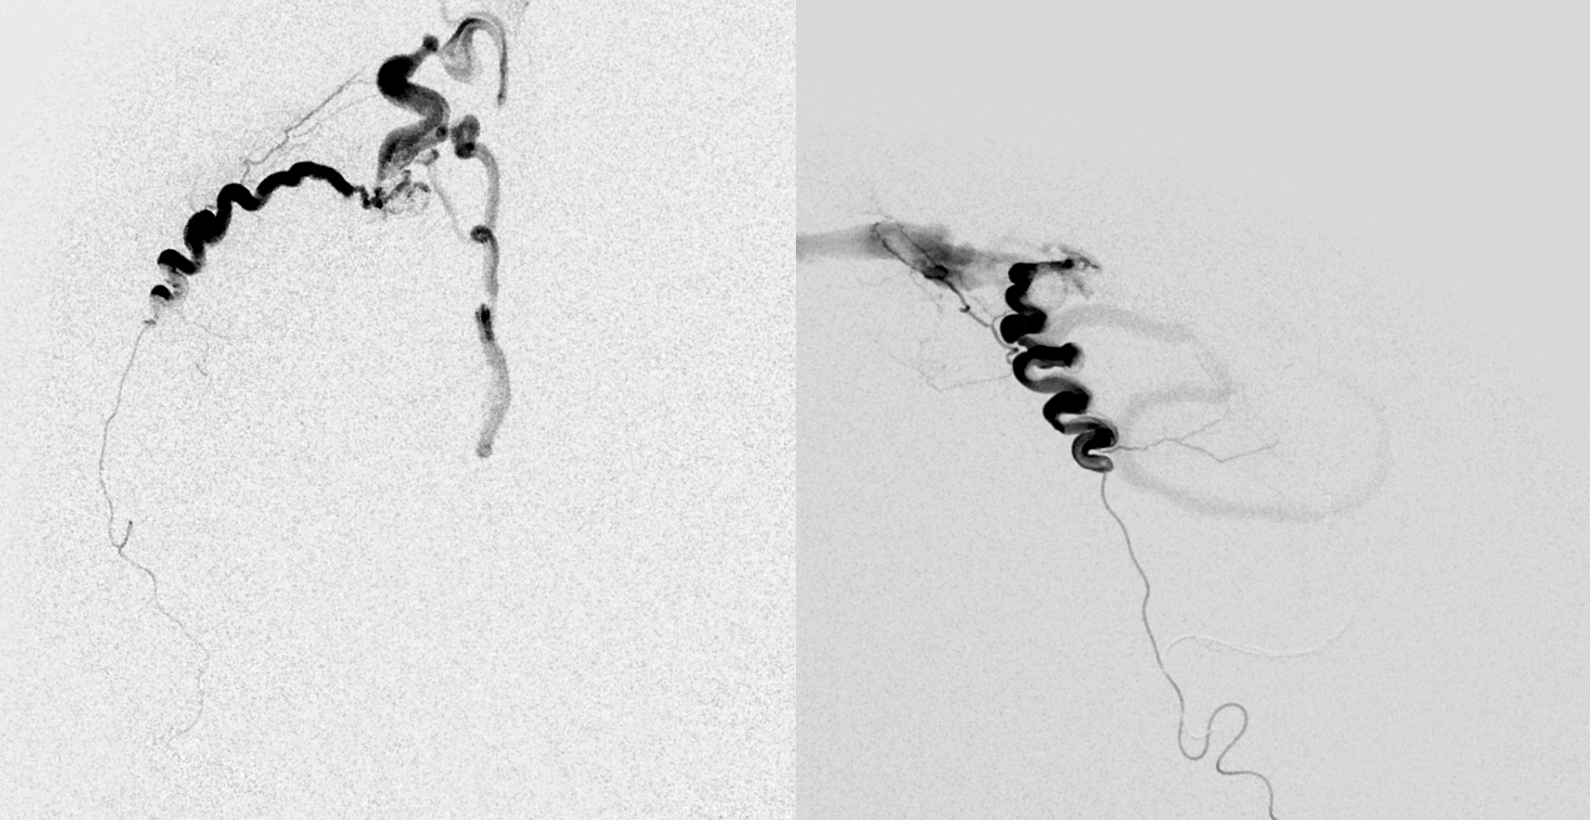

Closed

Now, look at the images below and tell me what the mistake during first injection was. The images on right should read post embo 1